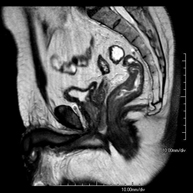

RM RectalProva diagnòstica no invasiva que consisteix en l'obtenció d'imatges d'alta definició anatòmica del recte mitjançant l'ús d'un camp electromagnètic i ones de ràdio (amb un emissor i un receptor). No utilitza radiació ionitzant. Normalment no requereix l'ús de contrast paramagnètic (Gadolini). Està indicada principalment en el diagnòstic, l'estadiatge i el seguiment del Càncer de recte.